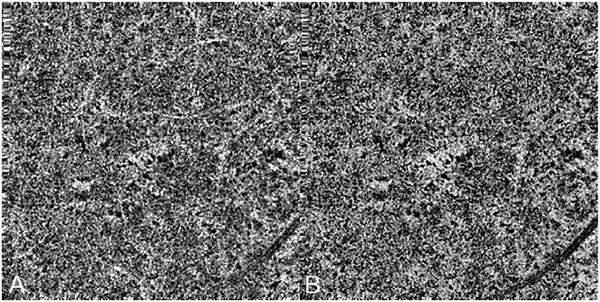

Optical coherence tomography (OCT) was one of the biggest advances in ophthalmic imaging. Building on that platform, OCT angiography (OCTA) provides depth resolved images of blood flow in the retina and choroid with levels of detail far exceeding that obtained with older forms of imaging. This new modality is challenging because of the need for new equipment and processing techniques, current limitations of imaging capability, and rapid advancements in both imaging and in our understanding of the imaging and applicable pathophysiology of the retina and choroid. These factors lead to a steep learning curve, even for those with a working understanding dye-based ocular angiography. All for a method of imaging that is a little more than 10 years old. This review begins with a historical account of the development of OCTA, and the methods used in OCTA, including signal processing, image generation, and display techniques. This forms the basis to understand what OCTA images show as well as how image artifacts arise. The anatomy and imaging of specific vascular layers of the eye are reviewed. The integration of OCTA in multimodal imaging in the evaluation of retinal vascular occlusive diseases, diabetic retinopathy, uveitis, inherited diseases, age-related macular degeneration, and disorders of the optic nerve is presented. OCTA is an exciting, disruptive technology. Its use is rapidly expanding in clinical practice as well as for research into the pathophysiology of diseases of the posterior pole.

光学相干断层扫描(OCT)是眼科成像领域的重大突破之一。在此基础上,OCT 血管造影术(OCTA)提供了视网膜和脉络膜血流的深度分辨图像,其细节水平远远超过了旧的成像方式。这种新的模式具有挑战性,因为需要新的设备和处理技术,目前成像能力的限制,以及成像和对视网膜和脉络膜成像及适用病理生理学的理解的快速发展。这些因素导致学习曲线陡峭,即使对于那些对基于染料的眼部血管造影术有一定了解的人来说也是如此。所有这些都是为了一种成像方法,它的历史还不到 10 年。这篇综述从 OCTA 的发展历史和 OCTA 中使用的方法开始,包括信号处理、图像生成和显示技术。这是理解 OCTA 图像显示内容以及图像伪影产生原因的基础。本文还回顾了眼部特定血管层的解剖结构和成像。介绍了 OCTA 在评估视网膜血管阻塞性疾病、糖尿病性视网膜病变、葡萄膜炎、遗传性疾病、年龄相关性黄斑变性和视神经疾病的多模态成像中的整合。OCTA 是一种令人兴奋的、颠覆性的技术。它在临床实践中的应用以及对后极部疾病病理生理学的研究中迅速扩展。